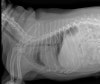

​수술 후 방사선 사진 / 출처: 라온동물메디컬센터

​수술 후 K는 약 1주일간 입원하며 집중적인 회복 관리를 받았습니다.

​입원 기간 동안 통증 조절, 상처 관리, 보행 상태를 지속적으로 모니터링했으며, 회복 과정에서 특별한 합병증 없이 안정적인 경과를 보였습니다. 입원 기간이 지나면서 우측 후지 보행이 점차 안정되었고, 퇴원 시점에는 정상 보행이 가능할 정도로 회복된 상태를 확인할 수 있었습니다. 이에 따라 보호자에게 수술 후 생활 관리와 주의사항을 안내한 뒤 퇴원을 진행했습니다.